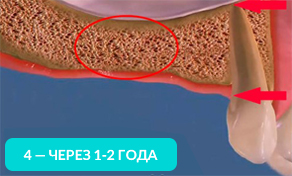

На 4-ом рисунке видно, что костная ткань стала значительно тоньше, теперь в это место уже невозможно установить импланты (потребуется операция по наращиванию костной ткани).

Обратите внимание, насколько тоньше стала кость на рисунке 4, как постепенно обнажается корень оставшегося зуба.

Убыль костной ткани распространяется на соседние зубы и их корни постепенно обнажаются!

Зубы, расположенные рядом с местом удаления, со временем становятся нестабильными и могут быть утрачены.